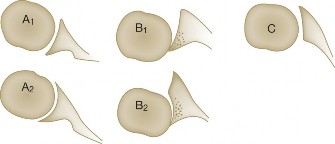

The correct answer is (D). Rotator cuff tears come in different shapes. Crescent-shaped tears are tears where the edge of the torn rotator cuff tendons form a crescent shape with an apex that points medially along the tension line of the rotator cuff muscles but is not retracted. Since this patient’s tear is not retracted, the tear is likely to be crescent shaped.

U-shaped tears (Answer A) look similar to crescent-shaped tears but the apex of the U extends further medially, usually to the edge of the glenoid in the sagittal plane.

An L-shaped tear (Answer B) resembles a tear that can be thought of as partially a crescent-shaped tear and partially a U-shaped tear. One leg of the L is the more mobile, less retracted, crescent-shaped tear which transitions into the other leg of the L, which is a less mobile, more retracted part of the tear which resembles a U-shaped tear.

Finally, a massive and immobile tear (Answer E) can be either U-shaped or longitudinal. These tears are greater than 5 cm in size and cannot be mobilized to the greater tuberosity.

Crescent-shaped tears are not retracted much medially, can be mobilized laterally relatively easily, and thus can be relatively easily repaired to humeral bone (see Fig. 2–13).

Figure 2–13_Crescent-shaped rotator cuff tear and repair. SS, supraspinatus; IS, infraspinatus. (Redrawn from Burkhart SS, Lo IKY. Arthroscopic rotator cuff repair. _J Am Acad Orthop Surg. 2006;14(6):333–346.)

U-shaped tears can be repaired using marginal convergence (Answer E). U-

shaped tears have an apex that extends further medially, usually to the edge of the glenoid in the sagittal plane, and this part cannot be mobilized all the way to the greater tuberosity. Because of this lack of mobility, these tears have to be repaired using marginal convergence, which is essentially zipping up the U from the apex toward the greater tuberosity using side to side sutures to bring together the anterior and posterior leaves of the U-shaped tear. In performing this marginal convergence, you essentially are converting a U-shaped tear into a crescent-shaped tear that can be relatively easily mobilized to the greater tuberosity, allowing it to be repaired (see Fig. 2–14).

Figure 2–14_U-shaped rotator cuff tear and repair using marginal convergence. SS, supraspinatus; IS, infraspinatus. (Redrawn from Burkhart SS, Lo IKY. Arthroscopic rotator cuff repair. _J Am Acad Orthop Surg. 2006;14(6):333–346.)

Finally, an L-shaped tear resembles a tear that can be thought of as partially a crescent-shaped tear and partially a U-shaped tear. One leg of the L is the more mobile, less retracted, crescent-shaped tear which transitions into the other leg of the L, a less mobile, more retracted part of the tear which mechanically and visually resembles a U-shaped tear. The retracted U-shaped part, like a normal U-shaped tear, must be repaired using marginal convergence. Then the remaining crescent-shaped part, like a normal crescent-shaped tear, can be mobilized laterally and repaired to bone (see Fig. 2–15).

Figure 2–15_L-shaped rotator cuff tear and repair using marginal convergence. SS, supraspinatus; IS, infraspinatus; RI, rotator interval; CHL, coracohumeral ligament; Sub, subscapularis. (Redrawn from Burkhart SS, Lo IKY. Arthroscopic rotator cuff repair. _J Am Acad Orthop Surg. 2006;14(6):333–346.)